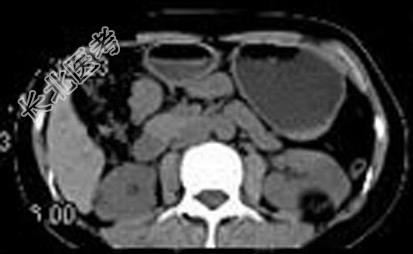

- 多项选择题女,38岁, 体检时B超在左肾探及一中强回声光团,边界清, 内部回声均匀,CT检查如图所示, 下列说法正确的是 ( )

A、左肾中部靠后方可见一类圆形低密度病灶

B、病灶与周围肾组织界限清楚

C、病灶密度为脂肪密度

D、考虑为左肾血管平滑肌脂肪瘤